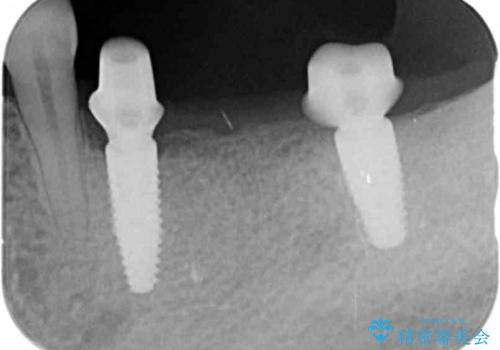

グラつきのある小臼歯は、抜歯を行い2本のインプラントを埋入することでしっかりと咬合機能を回復できる治療を計画します。

- 89.1万円(仮歯×3・ストローマンインプラント×3・フルジルコニアクラウン×3・チタンカスタムアバットメント×3)費用は治療当時の料金となります

インプラントは複数の奥歯を失った際に、咬合機能をしっかりと回復できる有効な治療です。